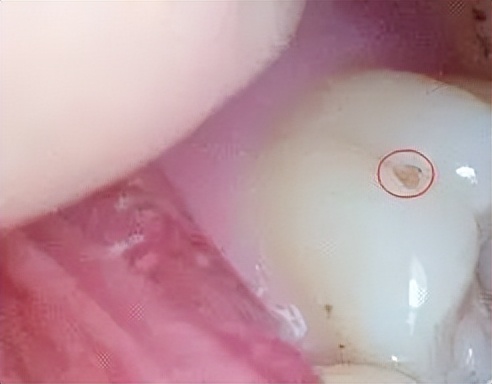

一般我们看到的龋齿是长这样的↓↓

运气好的话牙齿里面是这样的↓↓

运气不好的话,它可能是这样子的↓↓

所以眼见不一定为实,肉眼见到针孔大小的一个龋洞,可能牙齿里面已经被掏空。非专业人员请勿自己判断龋齿的情况, 就算再小的龋洞,都应该立刻补上。小洞不补,大洞吃苦。